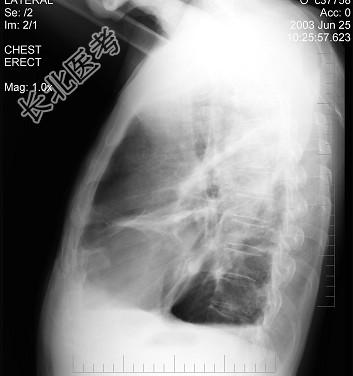

- 单项选择题男性患者,62岁, 常感胸闷、气逼,X线检查如图, 最可能的诊断是 ( )

A、右侧肺大疱

B、右侧气胸

C、右侧肺脓肿

D、右侧胸膜肥厚

E、气胸